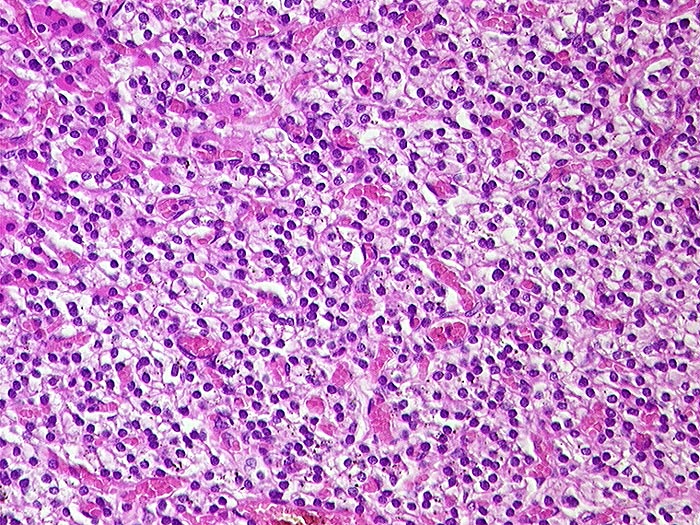

PathoPic ID 559 - Sekundärer Hyperparathyreoidismus: Hauptzell-Hyperplasie

Sekundärer Hyperparathyreoidismus: Hauptzell-Hyperplasie

Hauptzellen mit klarem Zytoplasma und kleinen runden Kernen. Fehlendes Fettgewebe.

Dialyse seit Jahren bei terminaler Niereninsuffizienz wegen Analgetikanephropathie.